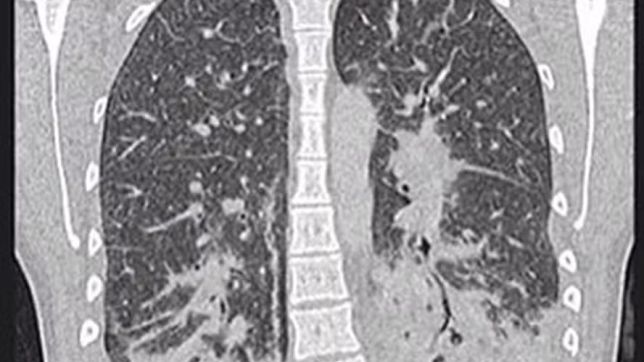

Ela foi inicialmente diagnosticada com pneumonia bacteriana grave, que foi tratada com antibióticos por cinco dias, porém, devido a não melhora dos sintomas, os médicos realizam um exame de raio-x que indicou manchas translúcidas por todos os pulmões, sugerindo que eles estavam cheios de líquido e apresentavam sinais de danos nos tecidos.

As imagens dos exames mostravam que a jovem tinha opacidades de vidro, geralmente ocorre junto com a consolidação nos pulmões. Consolidação se refere ao espessamento ou inchaço do tecido pulmonar, que acontece quando os espaços de ar nos pulmões se enchem de fluido, pus, sangue ou células.